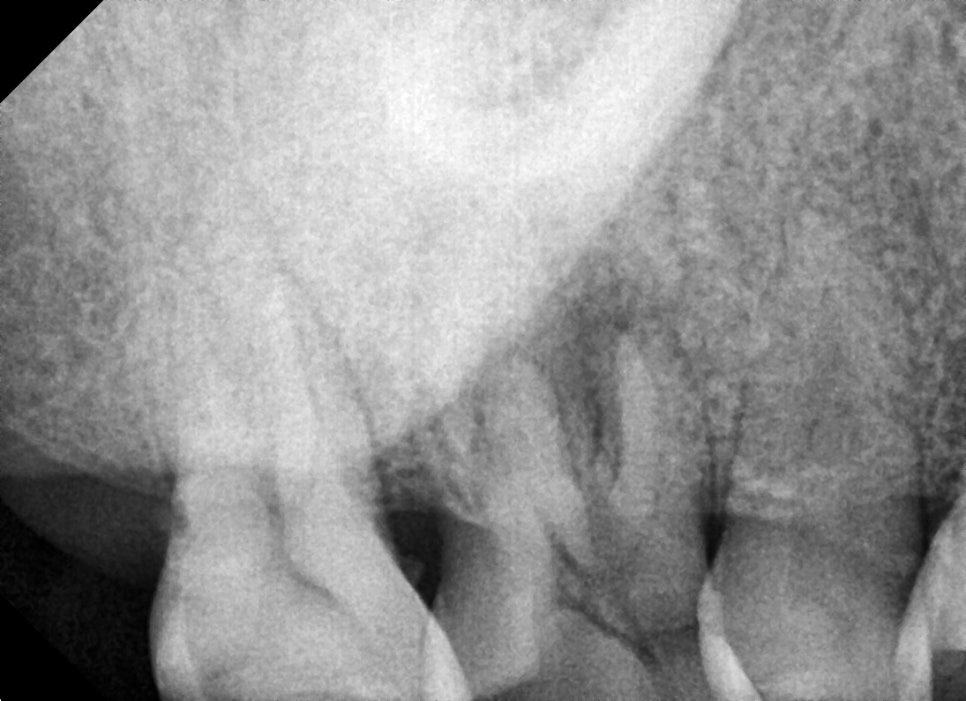

신경관 내 충전재의 길이를 사진 찍어가며 확인하고 신경치료를 마무리 한 사진입니다.

뿌리가 총 3개인데 3개의 신경관 모두 염증이 심하셨지만 최대한 소독하고 증상이 없는 상태에서 마무리하고

그다음으로 크라운을 제작하고 교합을 맞출 때 주변 치아의 마모도가 심하기 때문에 교합력을 균일하게 분산시키고,